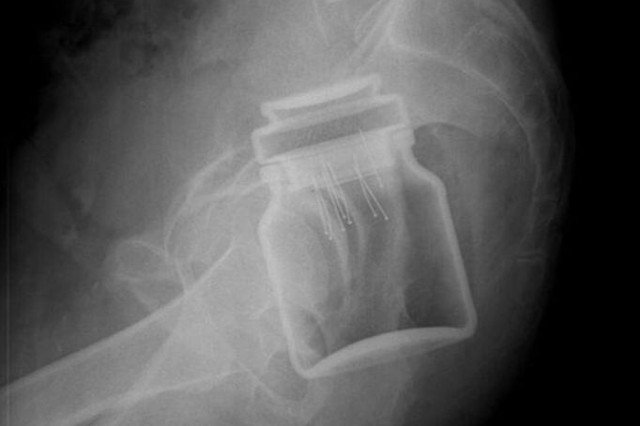

Ktoś zakrzyknie: "nic mnie już nie zdziwi", a inny wzruszy ramionami z niewinnym: "i co w tym dziwnego"? Wyobraźnia niektórych jest bardzo rozwinięta. Udowadniają to te zdjęcia rentgenowskie.

Na portalu radiopaedia.org lekarze udostępniają przypadki, z którymi mieli do czynienia w pracy. Chirurg z Sydney wspomina, że najdziwniejsze przedmioty, które znalazł w człowieku to butelka po Coca-Coli o pojemności 1,25 litra, dwa czerwone jabłka i latarka.

Równie ciekawe są wymówki. Jeden mężczyzna twierdził, że musiał załatwić potrzebę na świeżym powietrzu i przypadkowo przewrócił się na słoik, a prawnik z Georgii brał prysznic z telefonem komórkowym. Poślizgnął się i przedmiot po prostu "wbił się".